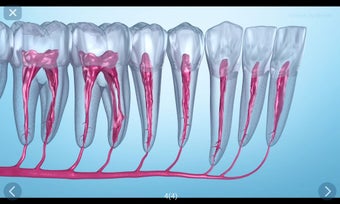

يستند التطبيق على مبدأ عرض الشرائح. يحتوي كل موضوع على 3-9 صور. يمكن عرض صور أي موضوع في أي وقت.